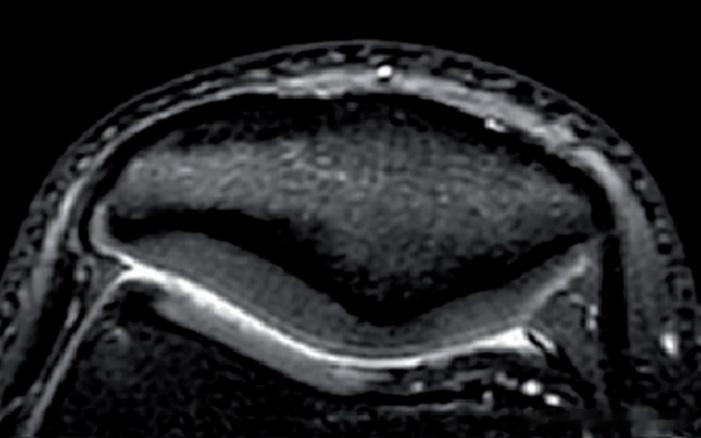

髌骨软化症 【髌骨软化康复】很多朋友膝盖疼痛,拍完核磁片子,然后对一些“专业术语

康复案例 【髌骨软化康复】在上海徐汇问诊治疗的小哥,也是一名爱健身的高中生小孩哥